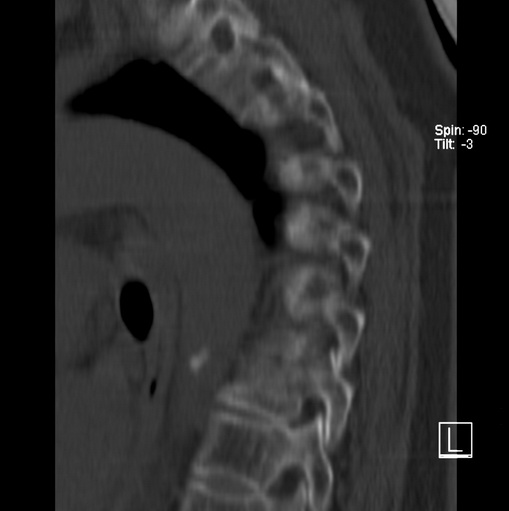

标题: CT25377:脊柱有无压缩骨折?

女、73、胸痛、胸闷3个月,无明显外伤病史,x线疑t4、t7陈旧压缩骨折,ct未经明显骨折,请问结论如何报?

老年女性病人,骨质稀疏,有些驼背,t4明显变扁,t7略变扁,椎体边缘无中断,骨小梁排列正常,无嵌插所致致密线。结合无明显外伤史,考虑老年骨质稀疏,慢性压缩改变,正如老年人骨质稀疏椎体呈双凹改变一样。我考虑报:老年骨质稀疏,t4、t7楔形变,脊柱曲度改变(驼背).敬请大家指教。